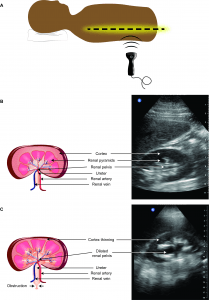

Point of care ultrasound (POCUS) was performed, with targeted views of the kidneys and bladder given the patient’s history of nephrolithiasis, as well as complete visualization of the aorta to the iliac bifurcation given the patient’s presentation with undifferentiated flank pain in accordance with emergency medicine POCUS recommendations [1-3]. The ultrasound revealing a large left renal stone with associated hydronephrosis (Figure 1A), a non-aneurysmal aorta, and an enlarged left iliac artery (Figure 1B, Video S1). The presence of the dilated left iliac artery prompted immediate consultative imaging rather than the common diagnostic pathway of next day outpatient consultative imaging. A CT scan confirmed the presence of multiple left-sided renal stones with hydronephrosis including a 2cm cluster in the renal pelvis (Figure 1C) and a 6.7cm ruptured left isolated iliac artery aneurysm (IAA; Figure 1D).

Figure 1. A) POCUS image of left kidney with large stone in the renal pelvis (blue arrow) and hydronephrosis. B) left iliac artery (blue chevrons). C) CT image of left kidney the renal pelvis stone (blue arrow) and lower pole non-obstructing stones (orange arrow) and D) left iliac artery with aneurysm (blue chevrons).

Video S1. First clip: left kidney with large stone in the renal pelvis and hydronephrosis. Second clip: left iliac artery.